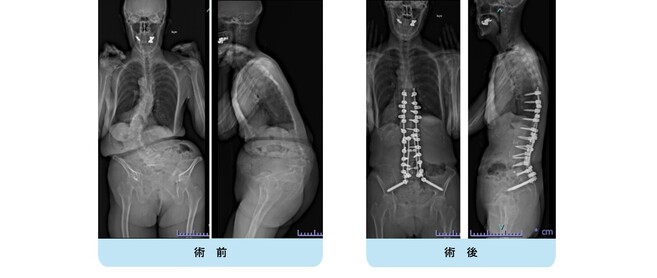

思春期特発性側弯症が高度に進行した症例です。最大側弯角度は113°であり、100°を超える側弯の手術は一般的に神経合併症が危惧されます。神経合併症を極力防ぐため、また侵襲を低減する目的で、同じ入院期間に2回に分けて段階的に矯正手術を行いました。1回目に最も側弯の強い箇所に対して側方から椎体間解離を行い、2回目に後方から全体のバランスが良くなるように慎重に矯正固定術を施行しています。

神経合併症はなく、術後の最大側弯角度は15°に改善(矯正率:87%)、背中の大きなコブも無くなっているのが分かります。(赤色矢印)

神経合併症が発生しないように慎重に手術を行うのは当然ですが、側弯を治すだけでなく横から見た姿勢を治すことにも留意しています。